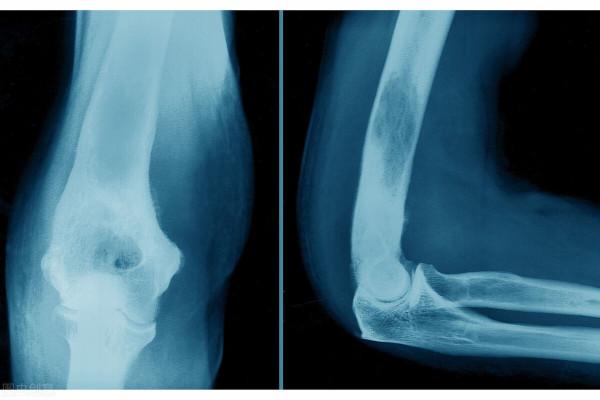

於當地醫院就診行MRI 示:右膝外側半月板損傷,伴半月板旁囊腫形成,右膝前叉韌帶損傷。入院查體:四測正常,右膝軟組織稍腫脹,過屈痛(+),外側半月板麥氏試驗(+),內側半月板麥氏試驗(-),前後抽屜試驗(-)。

入院診斷:右膝關節半月板囊腫。

發病年齡從5~83歲不等,以30~50歲男性為主,男女比例約3∶1,通常好發於大關節旁,以膝關節為主,在肘、肩、足部和踝等關節也偶有報道。